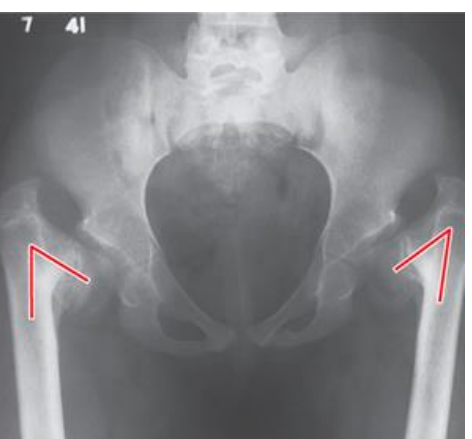

angle of inclination

-angle between the femoral neck and femoral shaft in the frontal plane

-adult normal ~125 degrees

-decreased angle = coxa vara <125

-increased angle = coxa valga >125 degrees

clinical implications of coxa vara

-increased hip joint stability

-increases moment arm of abductors (functionally stronger hip) reduces joint reaction force

-increase bending moment across femoral neck predisposition for (slipped capital femoral epiphysis or femoral neck fracture)

LE Chain effect of Coxa Vara

increased shear force across the femoral neck, adducted hip, valgus knee, pronation at foot, shorter limb